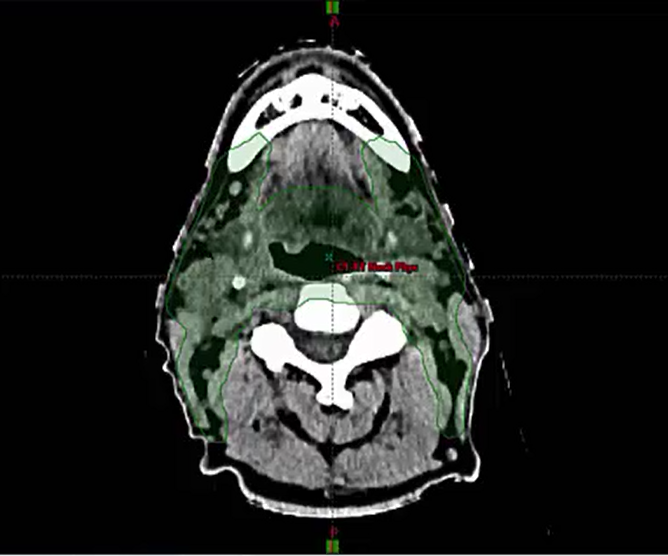

02/16/2023 - Dr. Cessal Kainickal - Radiation Oncology - India Head & Neck

PPF, maxilla, posterior, anterior, lateral, inferior, superior, medial, pterygopalatine ganglion, pterygomaxillary fissure, infratemporal fossa, ITF, PNI, sphenopalatine foramen, foramen rotundum, cavernous sinus. vidian canal, pterygoid canal, vidian nerve, artery, vein, pharyngeal canal, inferi...